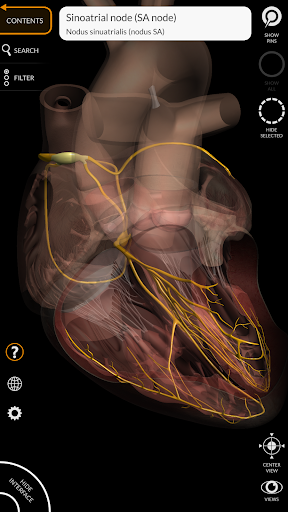

"Anatomy 3D Atlas" memungkinkan Anda mempelajari anatomi manusia dengan cara yang mudah dan interaktif.

Melalui antarmuka yang sederhana dan intuitif, Anda dapat mengamati setiap struktur anatomi dari sudut mana pun.

Model 3D anatomi sangat terperinci dan memiliki tekstur hingga resolusi 4k.

MODEL ANATOMI 3D

• Sistem kardiovaskular • Sistem